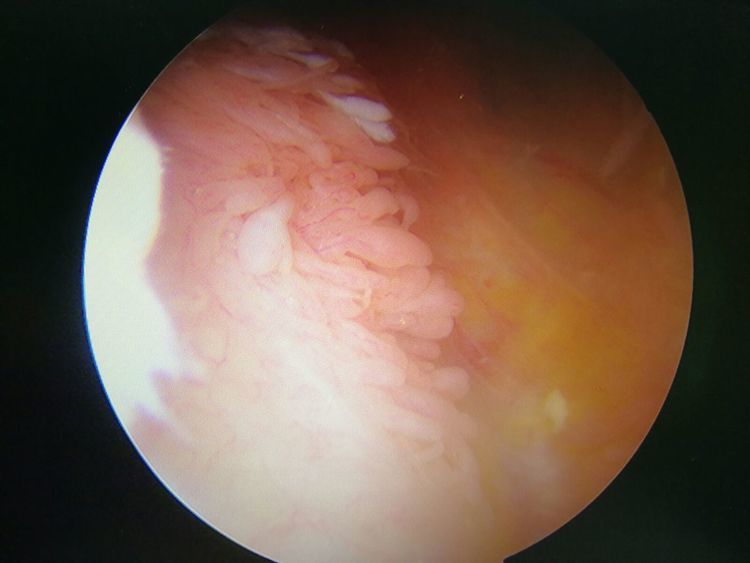

镜下手术图片,展示人体关节镜下情况:

骨科中心近两年共收治关节镜手术病人500余人,本人在近半年共收治关节疾病患者70余人,包括肩关节脱位及盂唇损伤、半月板损伤、交叉韧带损伤、叉韧带止点撕脱、髌骨脱位、色素性滑膜炎、关节游离体、老年骨性关节炎、踝关节外侧副韧带损伤伴距骨软骨损伤等。均通过关节镜或辅助关节镜手术治疗,短期内随访效果好,总体满意率在95%以上。